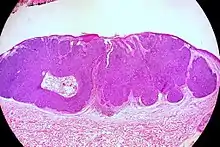

Micrograph of a basal-cell carcinoma, showing the characteristic histomorphologic features (peripheral palisading, myxoid stroma, artefactual clefting). H&E stain

Basal-cell carcinoma is named after the basal cells that populate the lowest layer of the epidermis due to the histological appearance of the cancer cells under the microscope.[16] Nevertheless, not all basal-cell carcinomas actually originate within the basal layer.[16] Basal-cell carcinomas are thought to develop from the folliculosebaceousapocrine germinative cells known as trichoblasts. Trichoblastic carcinoma is a term used to describe a rare and potentially aggressive malignancy that is also thought to arise from trichoblasts and may resemble a benign trichoblastoma (differential diagnosis can be challenging).[17][18][19] It has been suggested that lesions diagnosed as 'trichoblastic carcinoma' may actually themselves be basal-cell carcinoma.[20]

Basal-cell carcinoma cells appear similar to epidermal basal cells, and are usually well differentiated.[25]

Nodular basal-cell carcinoma (also known as "classic basal-cell carcinoma") accounts for 50% of all BCC.[27] It most commonly occurs on the sun-exposed areas of the head and neck.[28]:748[29]:646 Histopathology shows aggregates of basaloid cells with well-defined borders, showing a peripheral palisading of cells and one or more typical clefts.[27] Such clefts are caused by shrinkage of mucin during tissue fixation and staining.[30] Central necrosis with eosinophilic, granular features may be also present, as well as mucin. The heavy aggregates of mucin determine a cystic structure. Calcification may be also present, especially in long-standing lesions.[27] Mitotic activity is usually not so evident, but a high mitotic rate may be present in more aggressive lesions.[27] Adenoidal BCC can be classified as a variant of NBCC, characterized by basaloid cells with a reticulated configuration extending into the dermis.[27]